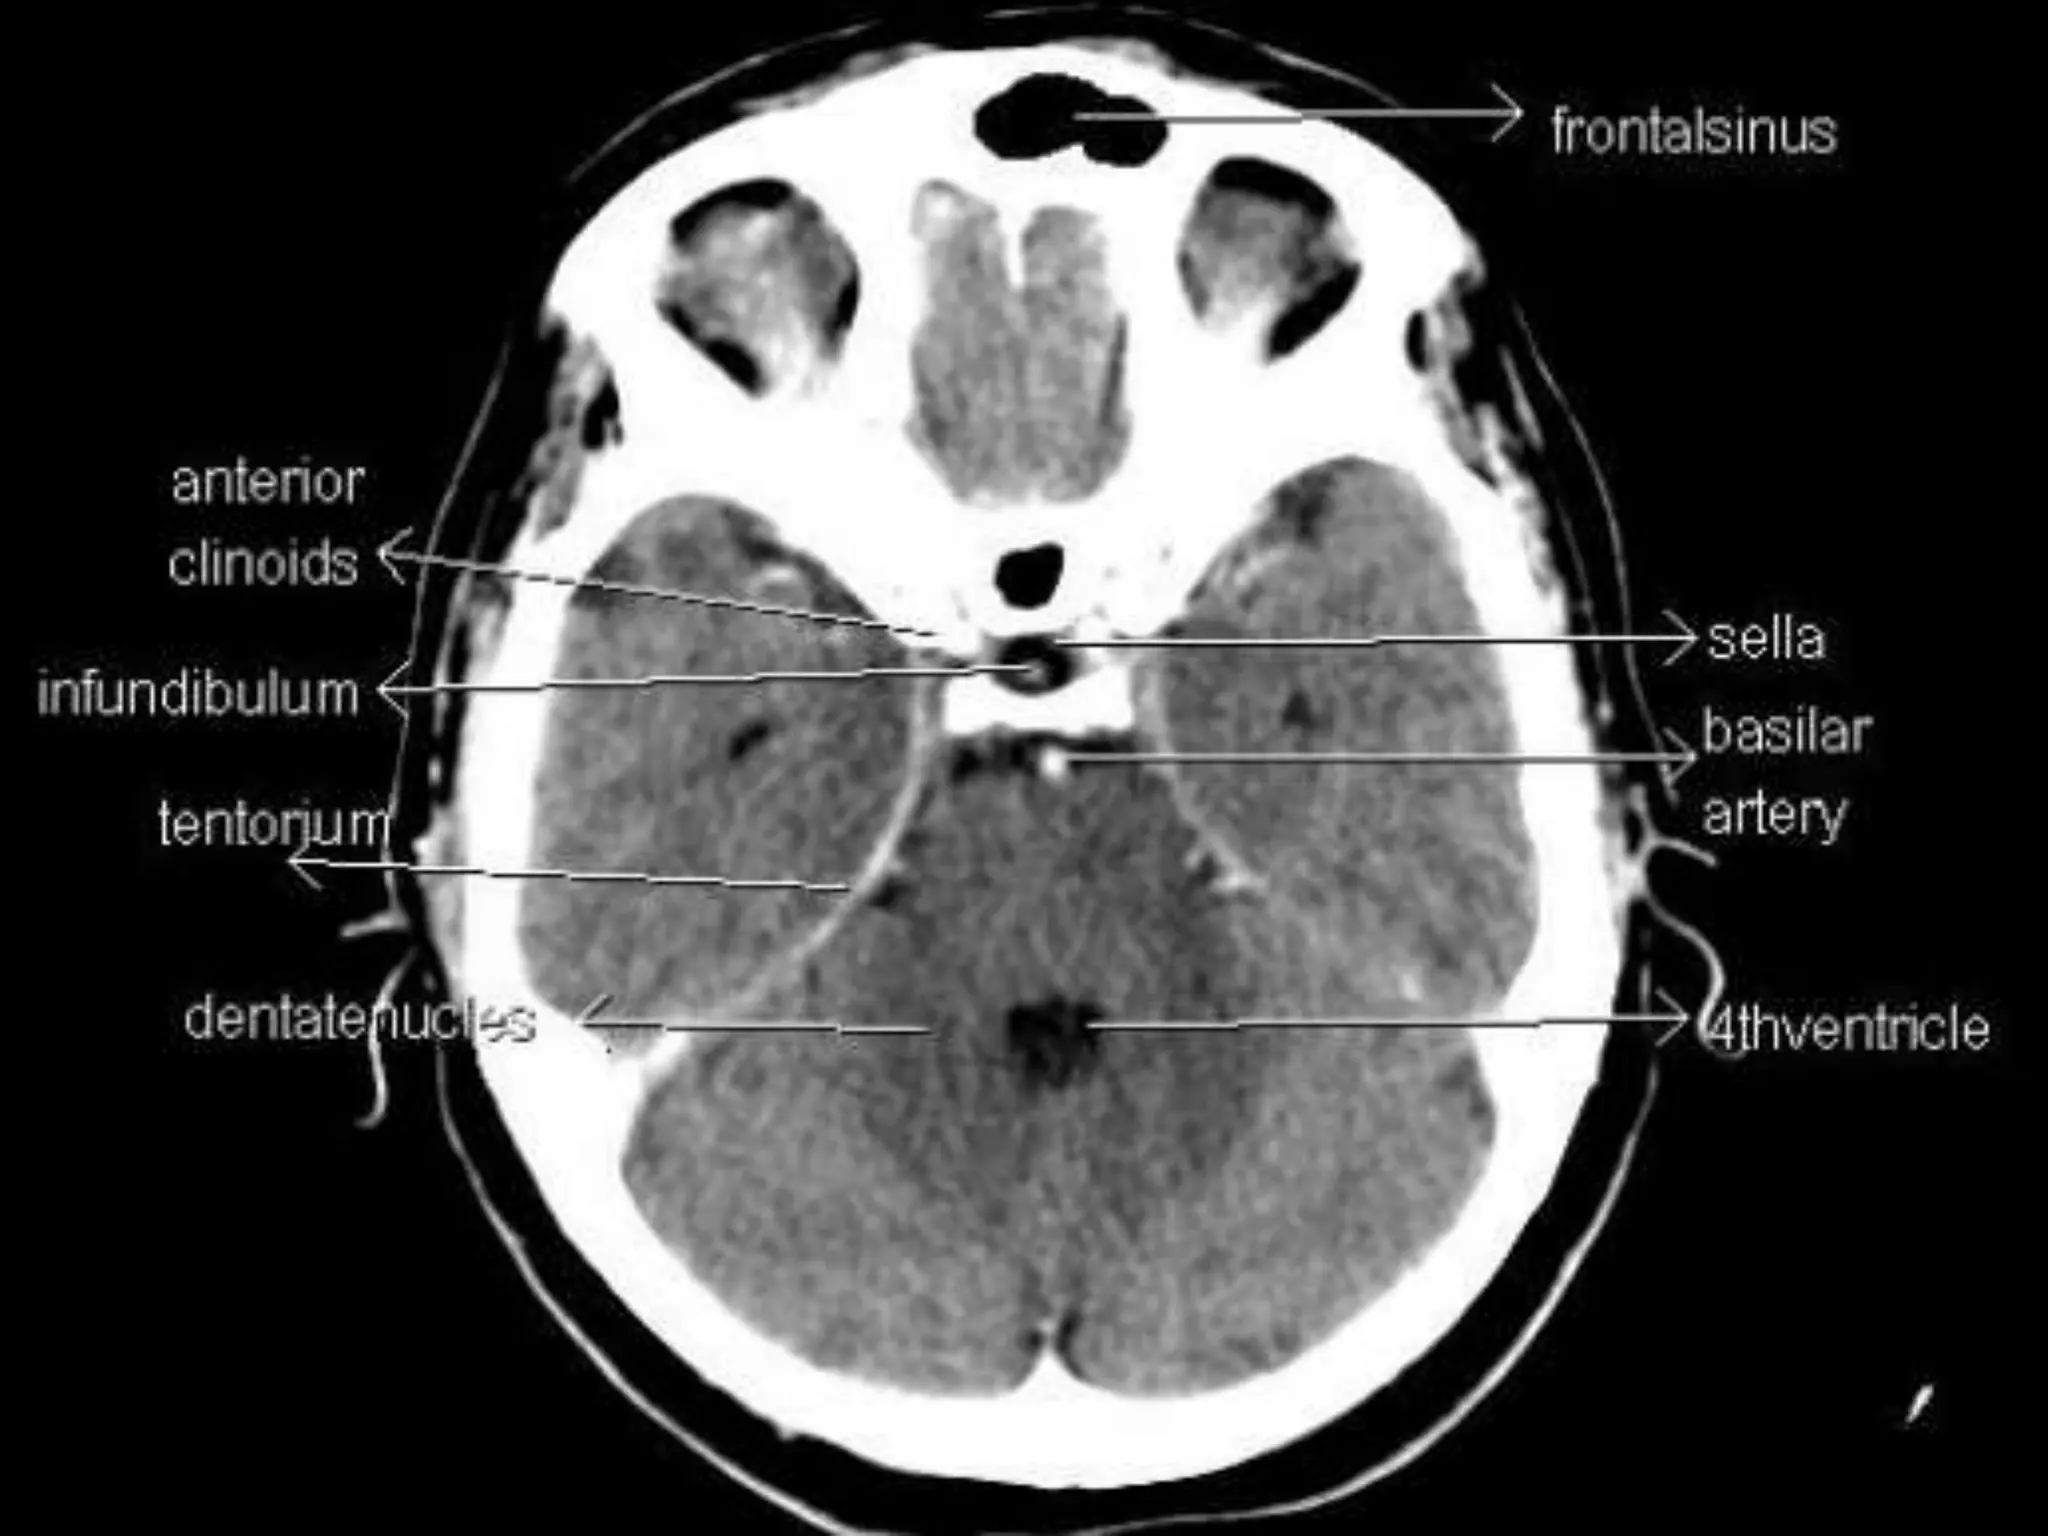

Axial CT Anatomy.

Sectional Anatomy: NormalAxial CT and MRI Anatomy. On CT and MR scans, the brain has been briefly viewed in infratentorial and supratentorial sections, as described below. CT scans are performed with a 15- to 20-degree angulation to the canthomeatal line at 8-mm increments. MRI scans are generally obtained parallel to the AC-PC line in the axial plane with 6-mm slice thickness. Using the sagittal view, the coronal sections are acquired parallel to the brain stem, and the sagittal sections are obtained perpendicular to the axial section. On MRI studies, cranial nerves IX and X can be demonstrated at this level because they emerge from the postolivary sulcus. The posterior aspect of the cerebellar hemispheres is outlined by the inferior portion of the cisterna magna.

In the parietallobe, there are a postcentral gyrus, a superior parietal lobule, and an inferior parietal lobule. The postcentral gyrus is a primary somesthetic area involved in general body sensation. In the temporal lobe, the superior, middle, and inferior temporal gyri are separated by the two transverse sulci. The posterior fossa contains the cerebellum and brain stem. The posterior fossa is outlined by the clivus and petrous bones anteroinferiorly, the tentorium cerebelli superiorly, and the occipital bone posteroinferiorly. The cerebellum is located posteriorly in the two thirds of the posterior fossa, separated from the brain stem by the fourth ventricle. The brain stem occupies the anterior third of the posterior fossa, including the midbrain, pons, and medulla oblongata. The brain derives its vascular supply via two carotid and two vertebral arteries. The internal carotid artery bifurcates terminally into the anterior and middle cerebral arteries. The two vertebral arteries unite at the caudal border of the pons to form the basilar artery.